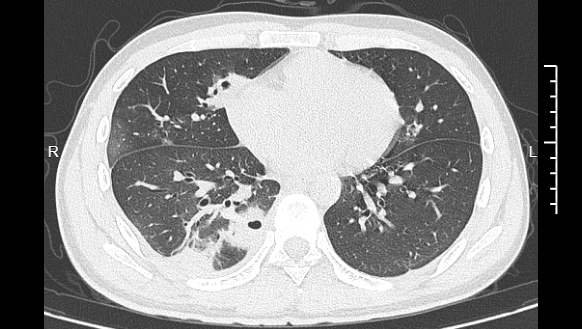

熬到第三天,小林已经烧到39℃,赶紧去医院就诊。接诊的主任医师丁群力一看他的症状,立刻安排了CT检查。结果显示:小林的肺里有十几个空洞,部分肺组织已经坏死,这是典型的血源性肺脓肿。

083901cp4kwnjkmkwbeznj.png 小林的CT影像显示肺里有多个空洞

进一步的细菌培养和基因检测揭开了真相,小林的血液里检出了金黄色葡萄球菌,这种细菌,就藏在每个人的皮肤表面。“‘罪魁祸首’就是那颗被挤掉的痘痘。”丁群力解释,“这颗痘痘长在脸部‘危险三角区’,挤痘痘时的压力把细菌推进了血管,引发了败血症,接着细菌顺着血流跑到肺部,侵蚀肺组织。”